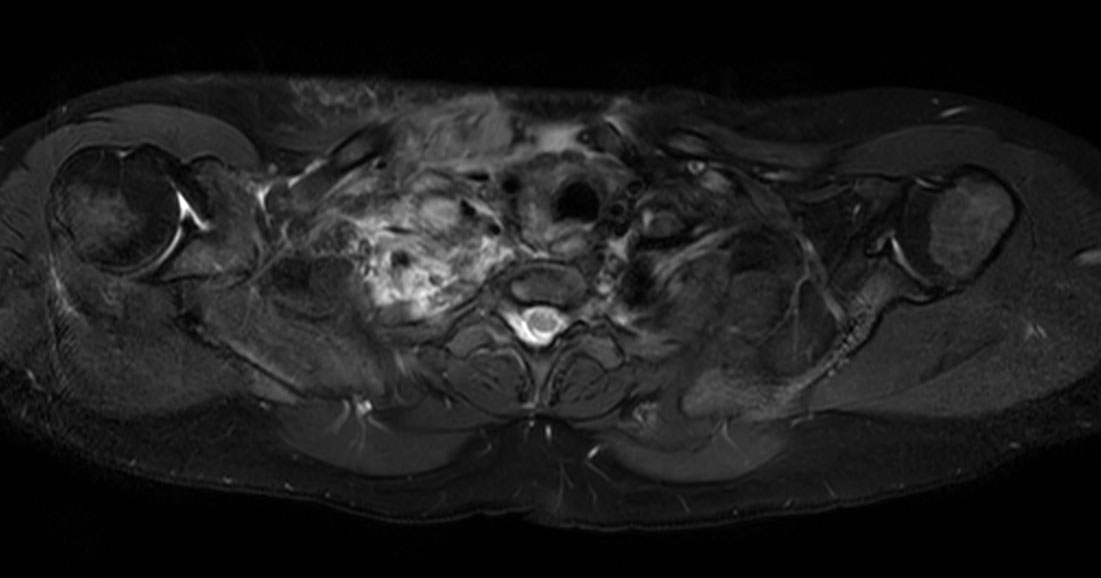

Patient referred to MRI post trauma of the HeadNeck region.

Axial T2w mDIXON XD TSE (In Phase)